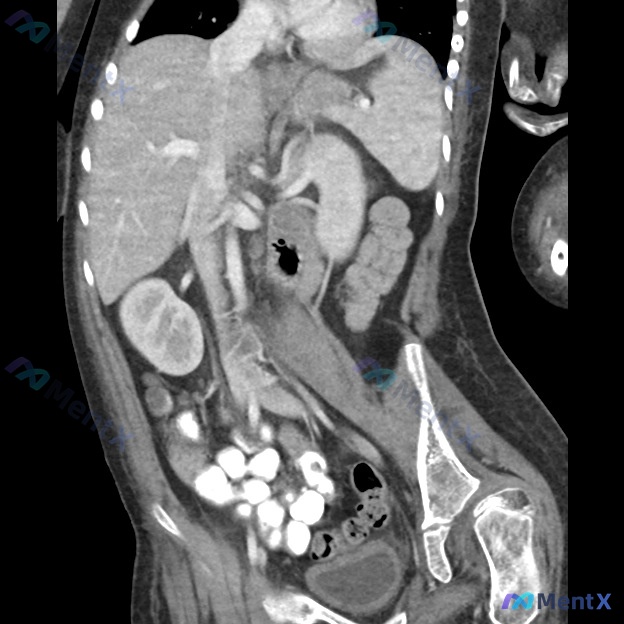

整理到一份有点纠结的病例资料,先放出来大家讨论。 基本情况:15岁男性,脑瘫,完全不能行走;无法在对抗重力的情况下保持头部直立;坐轮椅时感到明显疼痛。 影像:做了骨盆正位(AP)+ 尝试蛙腿侧位X线,还有术前CT。 影像描述提到:左侧股骨头形态不完整、塌陷,关节间隙变窄;左侧股骨近端及髋臼周围骨质密...